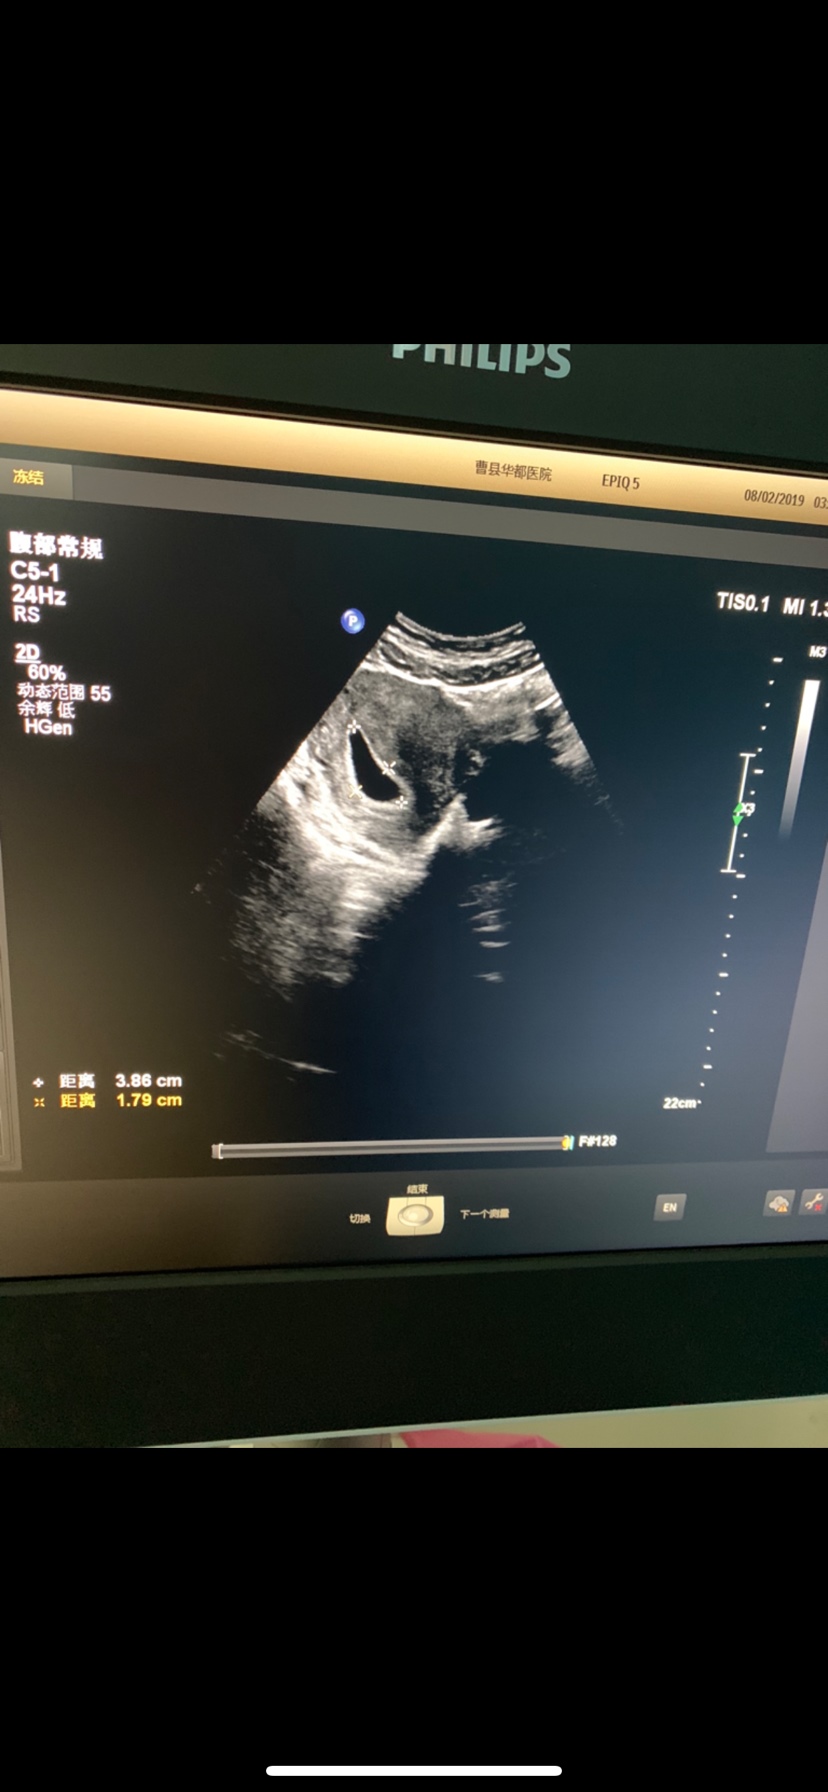

孕9周+1天